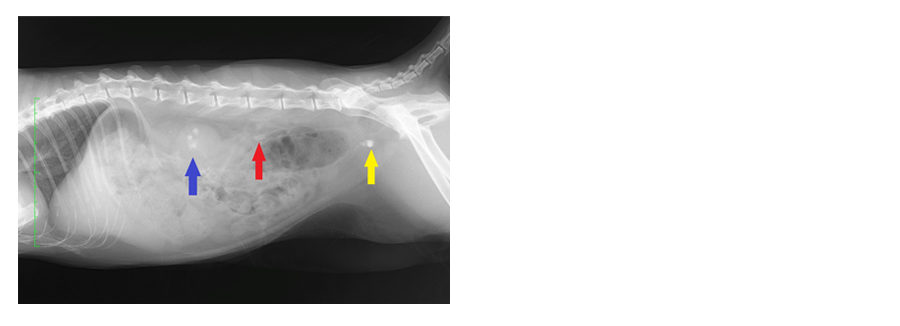

倉吉動物医療センター・山根動物病院&米子動物医療センター 腎泌尿器病

症例報告

犬猫の尿路結石症について|横浜市磯子区、金沢区のくりの木動物病院

猫の尿石症(尿路結石症)ってどんな病気? 猫との暮らし大百科